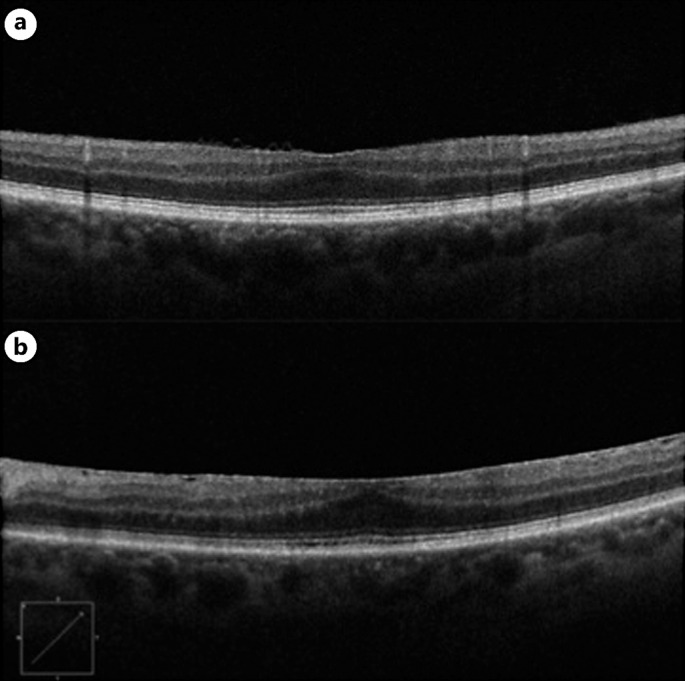

Case presentation: A 67-year-old man with no significant past medical history was referred to our retina clinic with a diagnosis of foveal hypoplasia. He had been experiencing significant vision loss for more than 1 year. OCT demonstrated absence of the foveal depression in both eyes. A subtle ERM was identified in the left eye OCT, but the presence of an ERM in the right eye OCT was equivocal. As such, it was unclear whether flattening of the fovea was attributable to hypoplasia or ERM based on OCT alone. This prompted further investigation with OCTA, which showed the presence of the FAZ in both eyes. The diagnosis of stage 2 ERM OU was made based on OCTA findings. The patient underwent cataract extraction with intraocular lens implantation, pars plana vitrectomy, and ERM peel, which resulted in improvement of visual symptoms and visual acuity. Follow-up OCT showed normalization of the foveal pit in the right eye greater than the left eye.

Conclusion: This case demonstrates the importance of utilization of OCTA in differentiating true foveal hypoplasia from this foveal "pseudo-hypoplasia" exhibited by our patient.